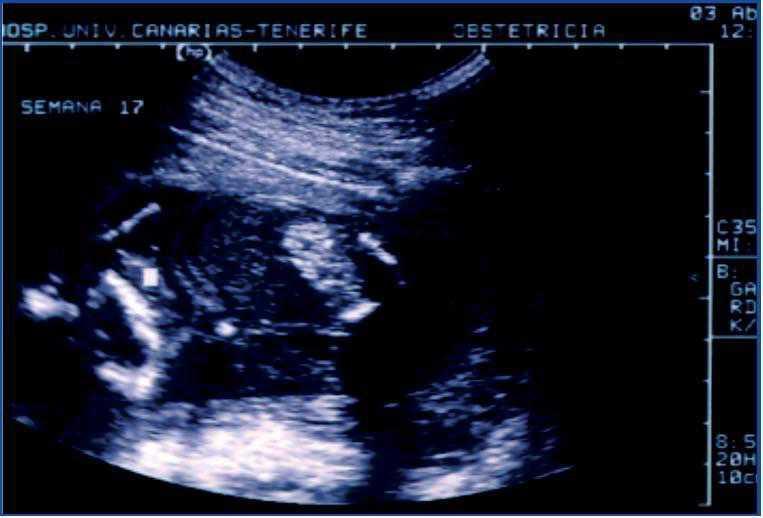

We had the opportunity of studying a child, currently three years old, who was referred by his paediatrician when he was five months old, after an episode of gross haematuria, which revealed the presence of a stone in the nappy. It was the first child of non-consanguineous parents, without any previous significant pathology, but with a history of renal colic on the paternal side of the family. Ultrasound foetal studies during pregnancy revealed a colon hyperechogenicity without other intestinal abnormalities (Figures 1 and 2), and a slightly increased nuchal luminescence, with no other findings of interest. As a result, a sweat test was performed at birth to rule out cystic fibrosis and the result was normal.

This is an early clinical presentation of cystinuria, reflecting the high lithogenic capacity of this condition. The particularity of the case is that the prenatal ultrasound found hyperechogenicity of the colon secondary to cystine crystal deposition. This form of presentation of cystinuria was described in 20063 and was subsequently confirmed.4 The explanation for this finding is that the cystine crystals are formed in the foetal kidney, they enter the amniotic fluid and are then swallowed. The ultrasound finding of the foetal hyperechogenic colon has been traditionally related to cystic fibrosis, which was why the studies needed to rule out the disease were performed at birth. The negative result and early clinical symptoms led to the diagnosis. Knowledge of this association may facilitate an early diagnosis of the disease, thus establishing an appropriate treatment.

Figure 1. Hyperechogenic intestine with sound density similar to foetal bone